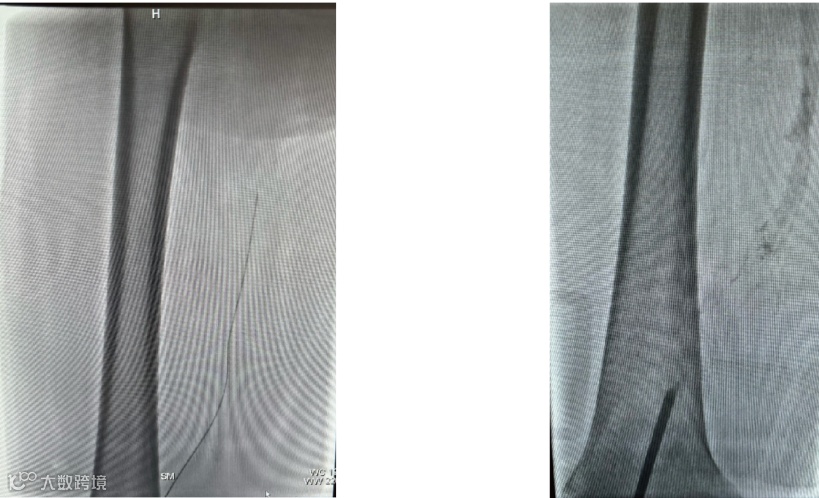

(一)患者取平卧位,常规消毒铺巾,右侧腹股沟区 1%利多卡因局部麻醉,Seldinger法穿刺右侧股静脉,置入6F 的血管鞘,导丝配合单弯导管至下腔静脉下端,经血管鞘造影,下腔静脉通畅,未见血栓形成。

(二)导丝交换置入长鞘,推送入腔静脉可回收滤器,路图模式下定位于肾静脉下缘释放滤器,再次造影见滤器形态位置满意。超声引导下穿刺左腘静脉成功,置入10F导管鞘,经鞘导入泥鳅导丝及单弯导管,反复尝试到达下腔静脉。

(三)导入大腔吸栓导管,经腘静脉吸栓至股总静脉,吸出大量血栓,造影后栓塞血管开通。

(四)导入球囊(10*80mm)扩张髂股静脉,再次造影见髂总静脉闭塞

(五)导入支架(14*90mm)覆盖髂总静脉压迫处,再次造影见髂股静脉通畅。拔除导管及导管鞘,术中出血约 300ml,术后患者安返病房。

造影可见:髂静脉 和股静脉血流复通